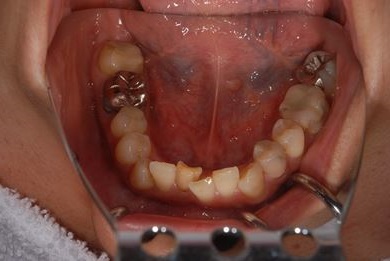

| 性別/年齢 | 女性 / 40歳 | ||||||||||||||||||||||||||||||||

| 主訴 | 前歯のさし歯の部分が目立ってしまい、新しくしたい。痛みも少しある。 | ||||||||||||||||||||||||||||||||

| 治療方針 | 保存不能な歯を抜歯し、セラミック治療にて、機能的・審美的回復を行う。 | ||||||||||||||||||||||||||||||||

| 治療内容 | ジルコニアフレームオールセラミッククラウン7本(オールセラミック用土台3本)、ハイブリッドセラミッククラウン1本、ハイブリッドセラミックインレー1本 | ||||||||||||||||||||||||||||||||